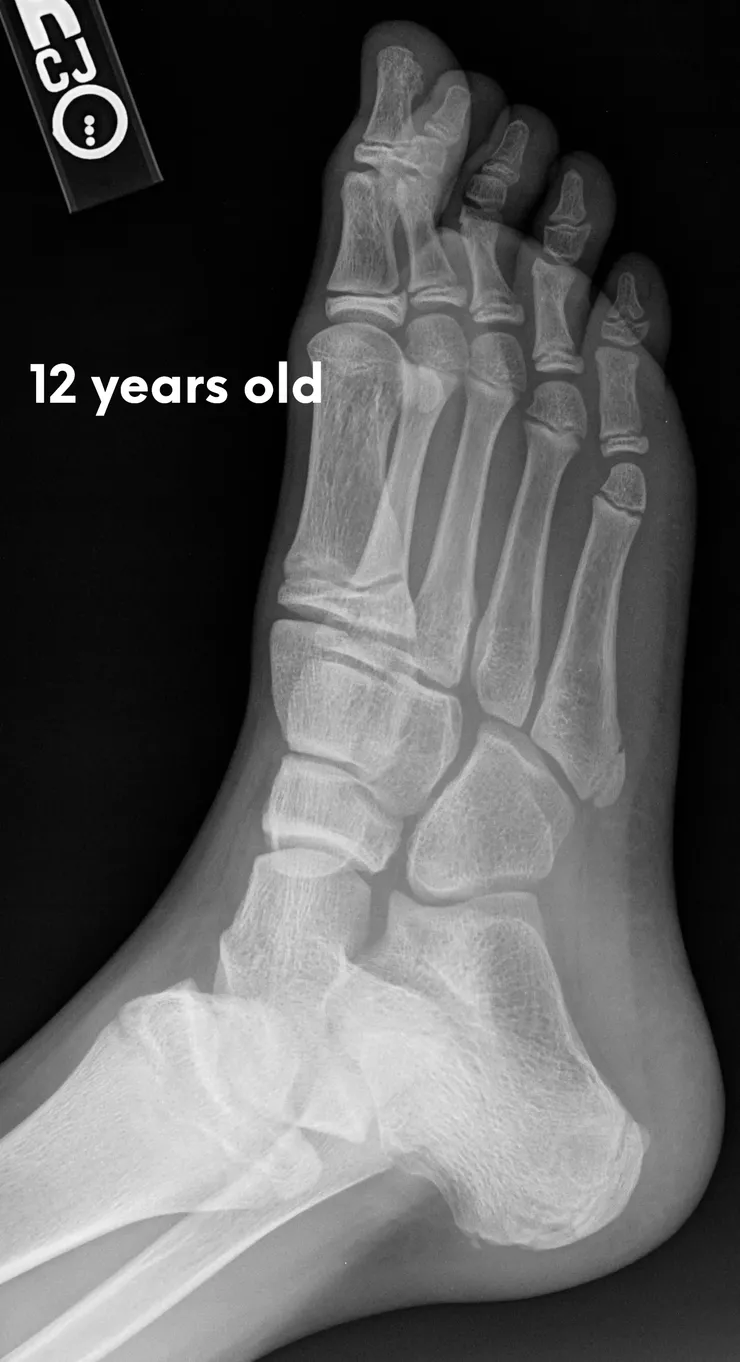

The pictures below will let you understand how babies' feet are developed. Here you can see how bones develop:

12 Years

18 YearsDear parents, children’s feet are developing structures, and the absence of an arch is a typical stage of development. Detailed X-RAY pictures above let us understand that babies' foot bones are not connected till the teen years. Only at the age of 14 may we consider that the bones in the feet have reached their connections. At the age of 18, we have fully completed foot structure, where muscles and bones create the whole support system.